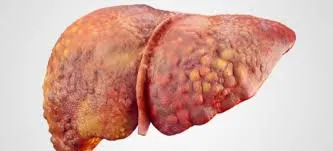

A DRPAD não é contraindicação à DP — e, na prática, muitos pacientes têm resultados comparáveis à hemodiálise. O “porém” está na mecânica: rins/hepatomegalia podem reduzir tolerância a volumes, aumentar risco de hérnias e extravasamentos, e piorar desconforto respiratório. Com técnica adequada (cateter presternal ou lateral, volumes menores, cicladora noturna e decúbito supino), a maioria das barreiras é contornável. Neste post, revisamos quando a DP é ótima, quando exigir cautela e como ajustar a prescrição para segurança e qualidade de vida.